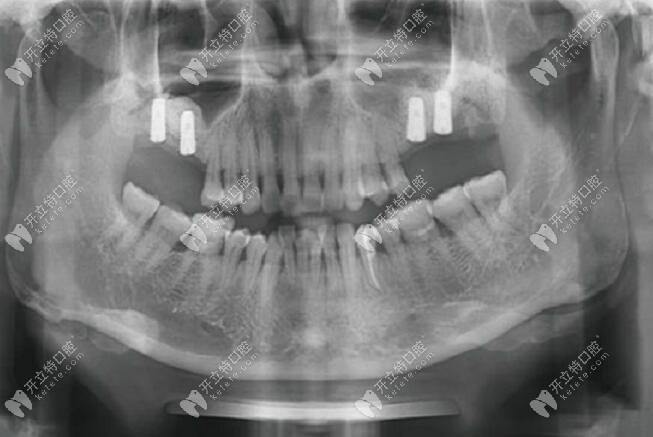

缺牙顧客簡介:女、51歲,上頜雙側(cè)的后牙缺失8年,做種植牙前戴的是活動(dòng)假牙;

口內(nèi)檢查:16、26、27號牙齒缺失,17號牙齒有3度松動(dòng),唇側(cè)及腭側(cè)的牙根暴露;18號牙2度松動(dòng),局部牙齦有輕微紅腫,28號牙1度松動(dòng)。

CBCT片檢查:16號牙位處測量竇嵴距為1.6mm;17號牙齒根尖周的牙槽骨有明顯吸收;26號牙位處測量竇嵴距為1.0mm;27號牙位處測量竇嘴距為1.6mm。

治療方案:雙側(cè)上頜竇外提升,17號做即拔即種(在拔牙窩植骨粉),同期16、17、26、27號植入韓國奧齒泰 TS3種植體;術(shù)后八個(gè)月進(jìn)行二期手術(shù),做個(gè)性化氧化鋯全瓷牙冠修復(fù)。

1、一期種植手術(shù):在上頜缺牙區(qū)逐級備洞,26、27號牙位植入韓國奧齒泰TS3種植體2顆(4.5mm*10mm),種植體邊緣與牙槽骨齊平。拔除17、18號松動(dòng)牙,在16、17號牙位植入韓國OSSTEM TS3種植體2顆(4.5mm*10mm)。

2、二期手術(shù):種植后八個(gè)月CT復(fù)查,口內(nèi)牙齦愈合良好、無明顯紅腫、種植體位置良好、上頜竇成骨良好,放置愈合基臺(直徑6mm、5mm,穿齦3mm)。